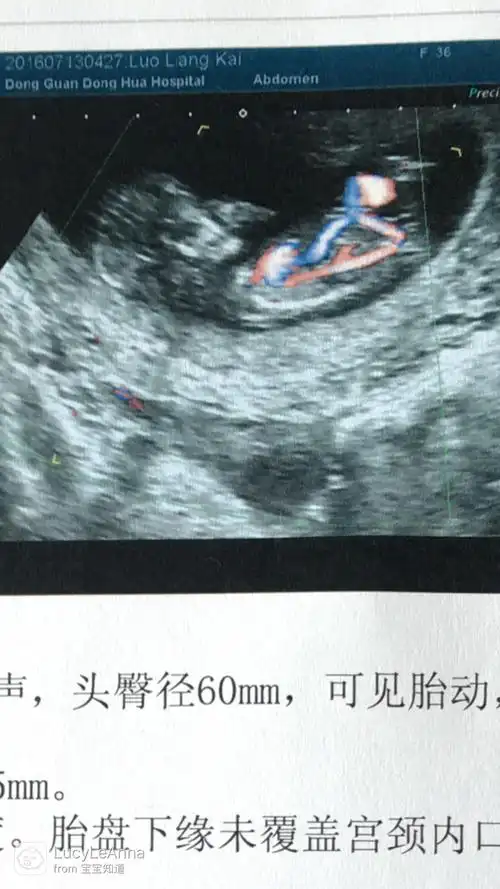

哪位会看男女?